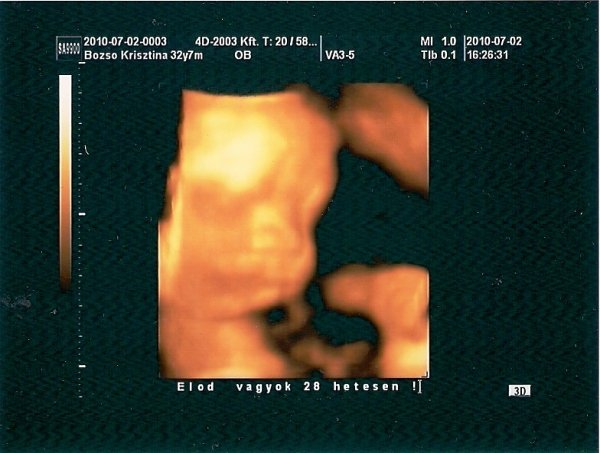

Voltunk a 4D-n, hatalmas élmény volt, álmomban nem gondoltam volna, hogy ilyen lesz. Minden rendben van, szépen fejlődik :)

Itt a kép is, megállapításunk szerint tiszta apja fia :)

Szuper lett az UH kép Kriszta! Nekünk nem lett, néha sajnálom. Szépen kivehető Előd arca.

Kriszta:szuper lett a 4D-s képetek a kis legényről,hát szerintem nem kis paraméterekkel fog megszületni már most olyan jó kis húsos nekem persze nem rossz értelemben :wink: !!!

Kriszti, édes a babóca :) és a szája tényleg a férjedé, ezt én is egyből megláttam!

Kriszti, nahát, egészen meglepődtem , hogy én is látok valamit a képből! Nagyon tetszik az Előd név, Ritával együtt mindjárt itt a nagy nap! Igazán irigylésre méltó dolog lehetett látni a kis csöppséget! El is hiszem, Rita, hogy már várod te is! Biztosan csodálatos lesz!

Előd baba nagyon aranyos a képen,és már mindjárt itt a vége!Hogy repül az ídő!